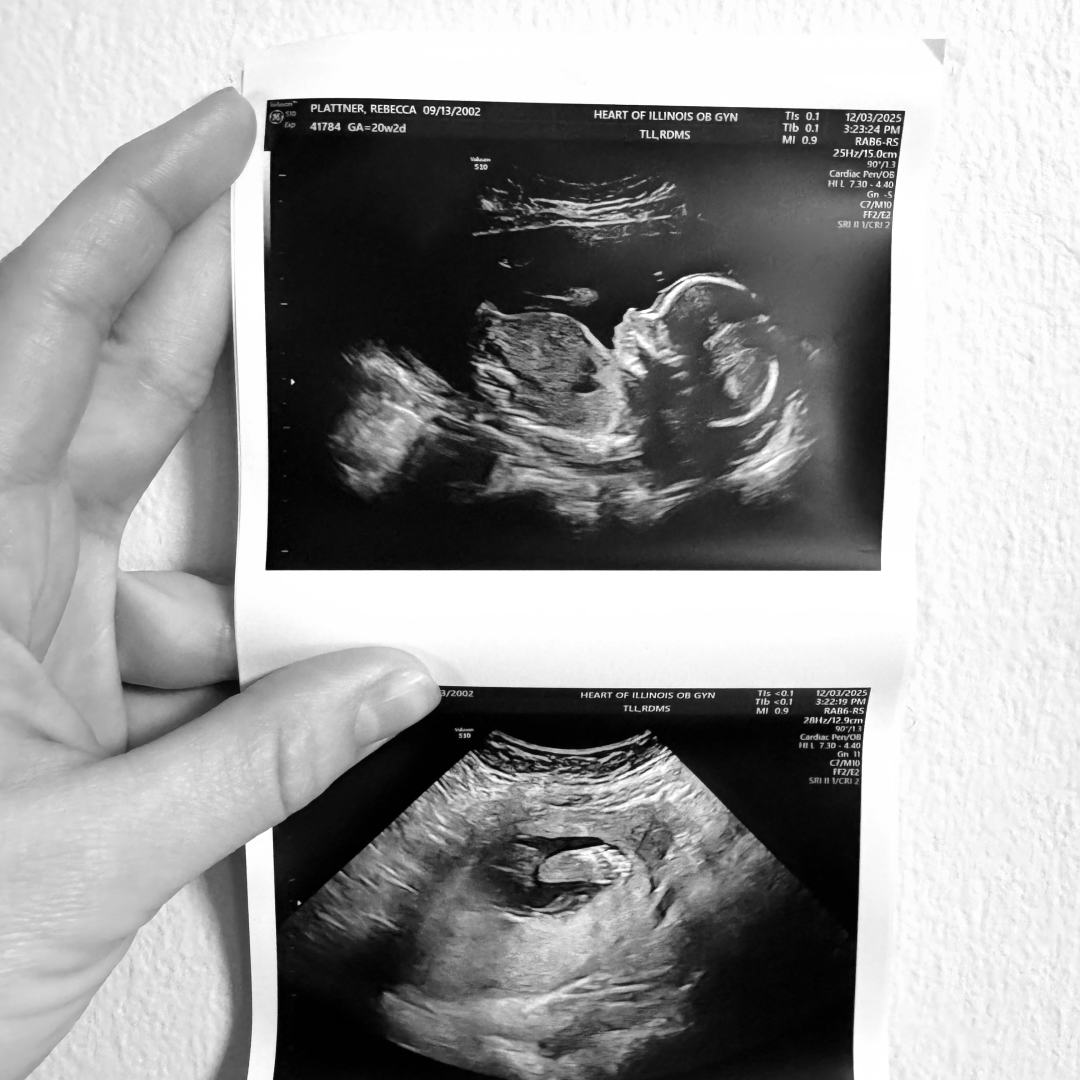

Rebecca's Baby Registry

Rebecca & Jesse Plattner

Tremont, IL

April 20, 2026

We are so excited to meet our baby boy in April!